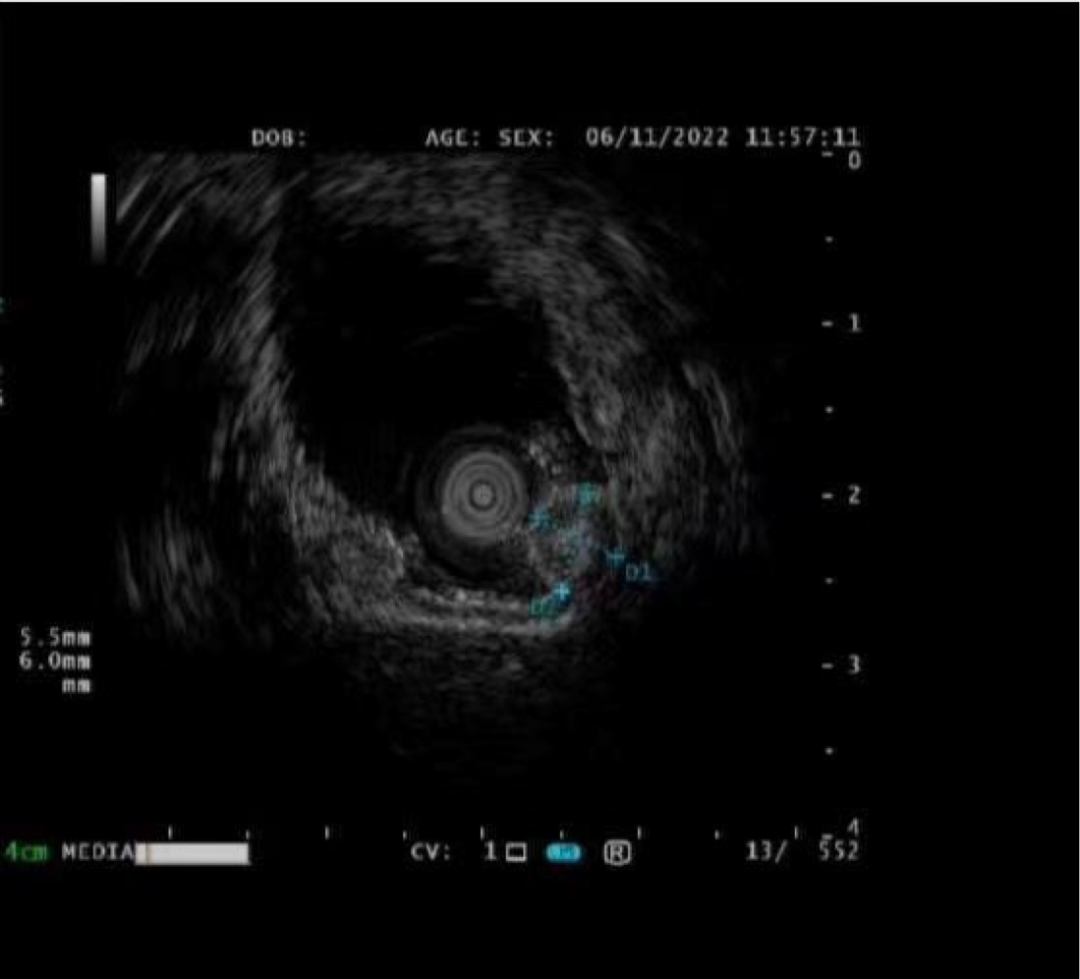

孙某某,女,65岁,因间断上腹痛10余天完善胃镜检查,胃体上段见两处直径0.5-0.8cm黏膜下隆起,超声内镜见病变起源于固有肌层,呈低回声改变,截面大小5.5*6.0mm。

考虑间质瘤,因有增大并恶变的风险,与患者家属详细沟通、解释病情,完成充分的术前评估及准备后,孙院长实施内镜下胃全层切除术,成功将病灶切除;术后病理诊断示“胃间质瘤,患者康复出院”。